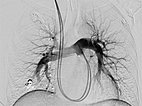

Über das Herz wurde vom Hals (transjugulär) eine Schleuse in die rechte Pulmonalarterie eingebracht, hierüber ein Koaxialkatheter. Nach Injektion von Kontrastmittel zeigen sich auch im rechten Unterlappen Lungenstrombahn pulmonale AVMs.

Die Abschluss-DSA über den Truncus pulmonalis zeigt keinen Zustrom mehr in die pulmonalen AVM.

Die Abschluss-DSA über den Truncus pulmonalis in der Parenchymphase bestätigt den vollständigen Verschluss der pulmonalen AVM.